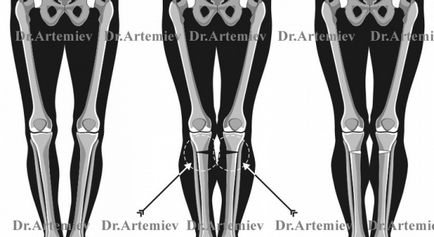

Javítás görbületi az eszköz nélkül,

Rendszer nagy javító osteotomiával, helyreállítását célzó alsó végtag tengely normál helyzetben

Változtatni az alakját a láb, azaz visszaállítja a normális helyzetben a mechanikai tengely az alsó végtag több szempontból is. Melyik módszer jobb, kényelmesebb, biztonságosabb?

Az általános elv korrekció deformáció, hogy a csont összekapcsolódik és metszik a kívánt pozícióba. A metszéspontja a csont (mesterséges törés) nevezzük osteotomia. A rögzítés a csont hívják fixálás. Tucatnyi módon kivésések és osteosynthesis száz módon. A modern traumatológia és az ortopédia, hogy helyes alakja az alsó végtagok használt 3 fő típusa osteosynthesis: lemezek, rudak, csövek. Elvileg minden ilyen módszerek, akkor lehet változtatni a helyzetét a tengelyen.